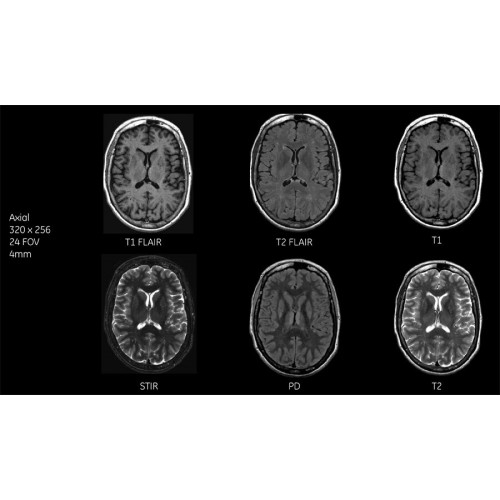

Система SIGNA Pioneer воплощает поразительные достижения в области визуализации. Передовая технология Total Digital Imaging (TDI) позволяет добиться большей четкости изображений и на четверть повысить соотношение сигнал/шум.

TDI построена на трех базовых компонентах:

• Технология Direct Digital Interface (DDI) использует независимый аналого-цифровой преобразователь для оцифровки сигнала от каждого из 97 радиочастотных каналов, что обеспечивает значительное увеличение качества за счет уменьшения фонового шума.

• Технология Digital Micro Switching (DMS) — это следующее поколение технологий радиочастотных катушек, основанное на замене аналоговых схем блокировки сверхбыстрыми микропереключателями (MEMS), что делает возможным быстрое переключение катушек для дальнейшего расширения возможностей визуализации с нулевым TE.

• Технология Digital Surround Technology (DST) — это новая технология объемной оцифровки данных, объединяющая сигналы от каждого элемента катушки. Прекрасное соотношение сигнал/шум и чувствительность поверхностных катушек в сочетании с превосходной однородностью и высокой проникающей способностью встроенной радиочастотной катушки — все это позволяет создавать качественные изображения не только позвоночника, но и всего тела.

Помимо технологии 97 РЧ-каналов, SIGNA Pioneer использует магнит 3.0Т высокой однородности, предназначенный для повышения качества визуализации во всех областях, а также закладывающий прочный фундамент для долгосрочных инвестиций и роста клинических возможностей.